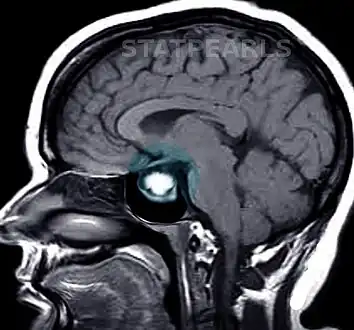

-

Invasive prolactinoma showing invasion into the left temporal lobe -

Prolactinoma on MRI